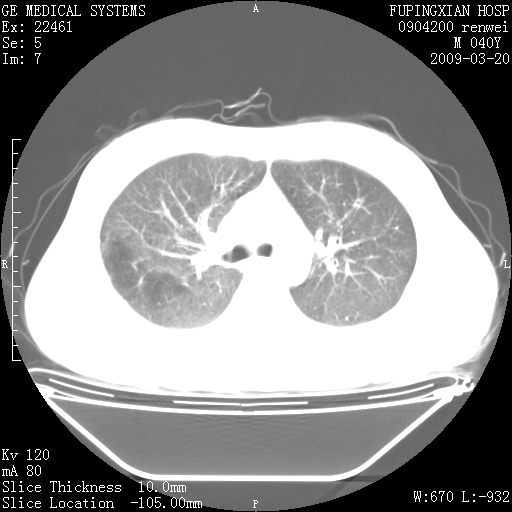

标题: CT18920:平时体健,体检时发现以下问题。 [打印本页]

标题: CT18920:平时体健,体检时发现以下问题。

单侧肺气肿表现,原因?   特发性或先天性可能

右肺气肿。

右肺局限性肺气肿

右肺局限性肺气肿。

右肺局限性肺气肿,有无呛咳史?

右肺局限性肺正常

双肺弥漫磨玻样改变,肺纹理增重,考虑早期间质纤维化伴局部阻塞肺气肿,[考虑黏液栓]

右肺局限性肺气肿;[考虑黏液栓]所致。

透明肺

双肺弥漫磨玻样改变,右肺局限性肺气肿。病人没有症状?

考虑间质性肺炎伴右侧局限性肺气肿,

右肺局限性肺气肿;[考虑黏液栓]所致

先天性支气管闭锁

右肺局限性肺气肿,原因?先天支气管闭锁?粘液栓?